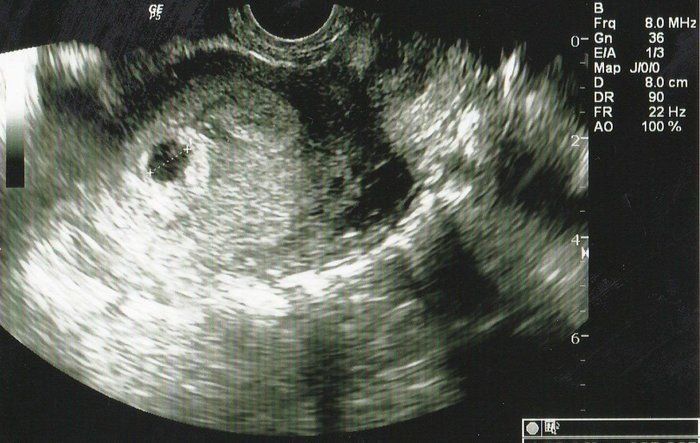

くろみつさんの妊娠4週目のエコー写真 直径9mmの小さな、小さな胎嚢を確認

妊娠検査薬で陽性反応が出たので、夫が休みの週末を待って2人で病院へ行きました。左上部に見える黒い丸が妊娠した目印となる胎嚢です。「やっと妊娠できた」という、うれしさはもちろんありましたが、小さな命が自分のおなかの中にあるということが信じられず、他人事のような不思議な感覚でした。